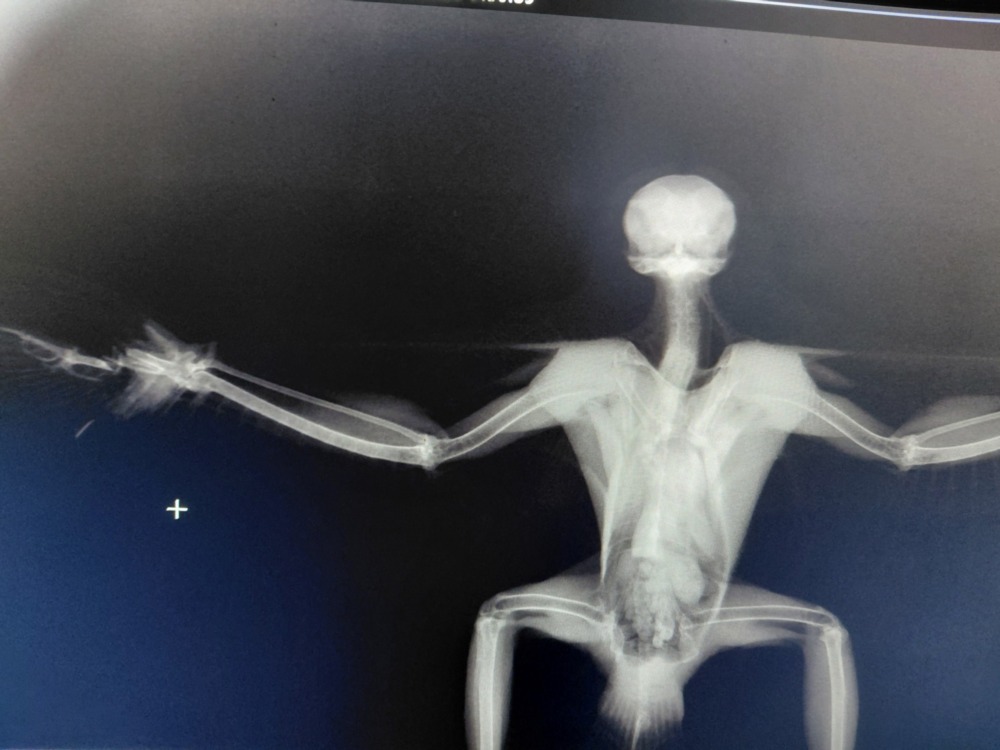

«Заключення – нажаль наш птах – захисник не зможе повернутись на волю. Перелам крила, що він отримав коли збив дрон, неможливо виправити. Кістки та м’які тканини сильно пошкоджені», повідомили у ветклініці.

Спеціалістом розглядався варіант ампутації пошкодженої ділянки крила, що б значно прискорила його видужання. Але саме цей вид дуже погано переносить наркоз. До того ж птах-захисник має легкий струс мозку. Тому фахівці ухвалили рішення, щоб загоєння проходило самостійно.